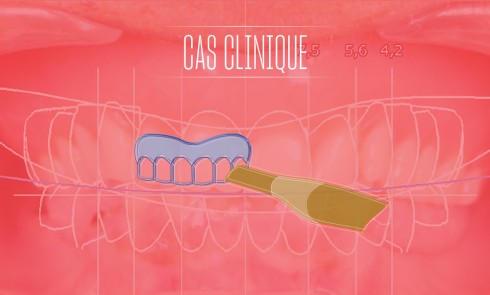

Le coffrage est garant de la conservation des données enregistrées, particulièrement au niveau des bords de l’empreinte (limites, épaisseurs…). Il est réalisé de la manière suivante (fig. 1a, b) :

• à l’aide d’une plaque de cire carrée (5 x 5 mm ; Palax Natural), l’empreinte est coffrée sur l’ensemble de sa périphérie, en prenant soin de bien dégager les bords modelés par le jeu musculaire ;

• le coffrage est terminé avec une bande de cire (3 x 5,5 mm), collée perpendiculairement à la première ;

• pour faciliter le coffrage au niveau lingual mandibulaire, le prothésiste s’aide de pâte à modeler ou de silicone lourd ;